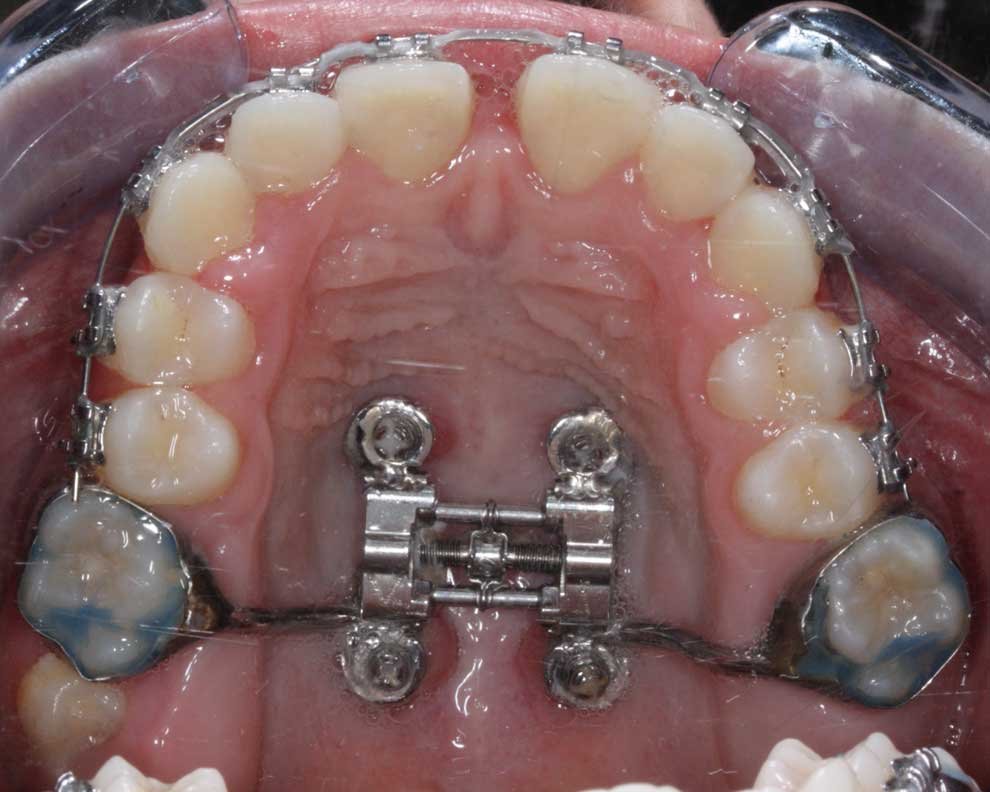

Maxila Estreita

Uma maxila estreita ou subdesenvolvida reduz o espaço na cavidade nasal e nas vias aéreas superiores.

Impacto na respiração:

Uma maxila estreita muitas vezes obriga as pessoas a respirar pela boca, pois o fluxo de ar nasal fica restrito. Isso pode resultar em apneia obstrutiva do sono (AOS) em alguns casos. Os sintomas relacionados incluem ronco, respiração bucal crônica e baixa qualidade do sono.

Expansores como MARPE (Expansor Rápido do Palato Assistido por Miniparafuso) para adultos e Hyrax para crianças ajudam a alargar a maxila, melhorando o fluxo de ar nasal e aliviando os sintomas.